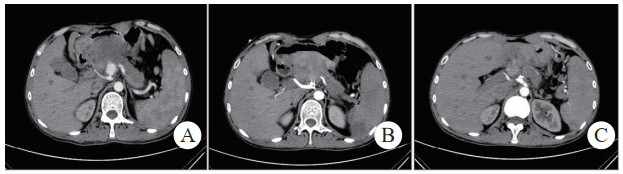

治疗后随诊复查CT显示,患者载瘤动脉及瘤腔内可见栓塞弹簧圈,血肿、假性动脉瘤瘤体体积明显缩小,未见血管再通与假性动脉瘤破裂,见图 2(病例2)。

| 注:图 2病例2 A为患者术前CT增强扫描,示胰腺炎影像,腹腔内见一血肿影,脾动脉起始段可见一瘤样扩张,内见对比剂填充;B、C分别为患者术后3 d及术后1个月复查CT增强示,血肿较前减小,原瘤样扩张处可见弹簧圈影及未见对比剂外溢 图 2 病例2术前、术后CT平扫及增强 |